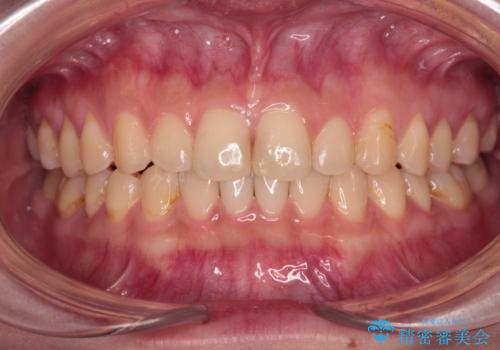

- 八重歯を気にして来院された高校生の患者様です。

ボディーコンタクトの激しい部活動を行っているため、補助装置とインビザラインを用いて、部活動を継続しながら治療を行うこととしました。

八重歯を効率よく改善するため、補助装置を使用して上顎の奥歯を後方に移動させました。

部活動をしながらでしたが、マウスピースをしっかりと装着してくださったので、1年半程度で終了することができました。